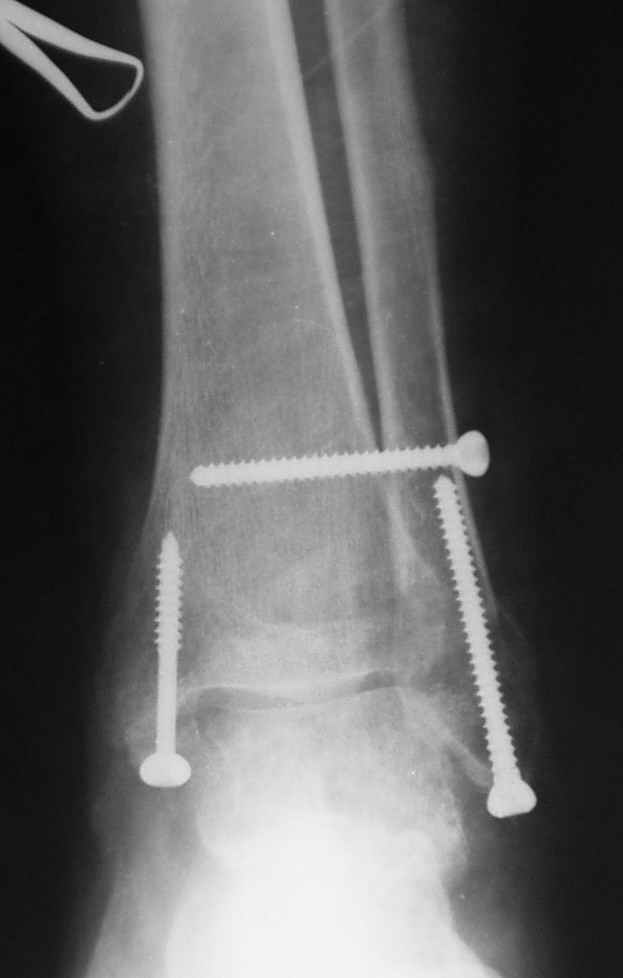

Ниже рентгенограммы

Операция 29 июля